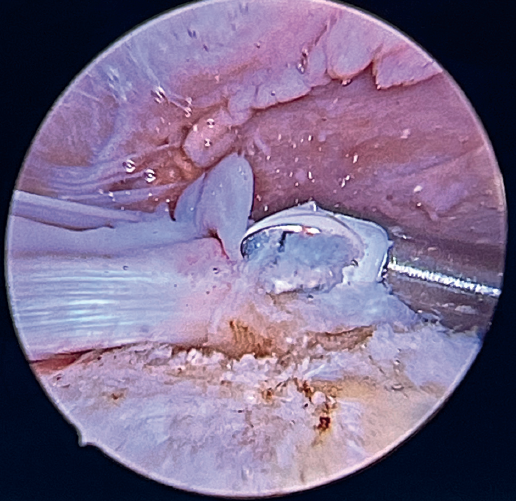

The glenoid origin of the LPB is preserved at all times. In the anterolateral zone of the greater tuberosity, we implant an anchor loaded with three sutures (FiberTak® 2.6 mm, Arthrex, Naples, FL, USA), more medial to the reflection zone of the LPB. To ensure correct guidance at implantation, we create a superolateral accessory portal without a cannula, close to the limit of the acromion.

Using penetrating forceps through the anterior portal, the surgeon penetrates the LPB and retrieves one of the suture threads, performing a self-locking Lasso suture in the same step. This is done with two of the three anchoring threads to ensure a correct LPB grip to the footprint of the greater tuberosity and that the tendon does not fray; we do not cut the two threads after knotting (Figures 4, 5 and 6). We also consider it very important to apply the biceps tendon, keeping it as flat and anatomical as possible, avoiding twisting or excessive distension of the tendon. Subsequently, a tenotomy of the LPB distal to these sutures is performed (Figure 7), thus allowing the LPB to function as a superior capsular reconstruction, restricting the ascent of the humeral head.